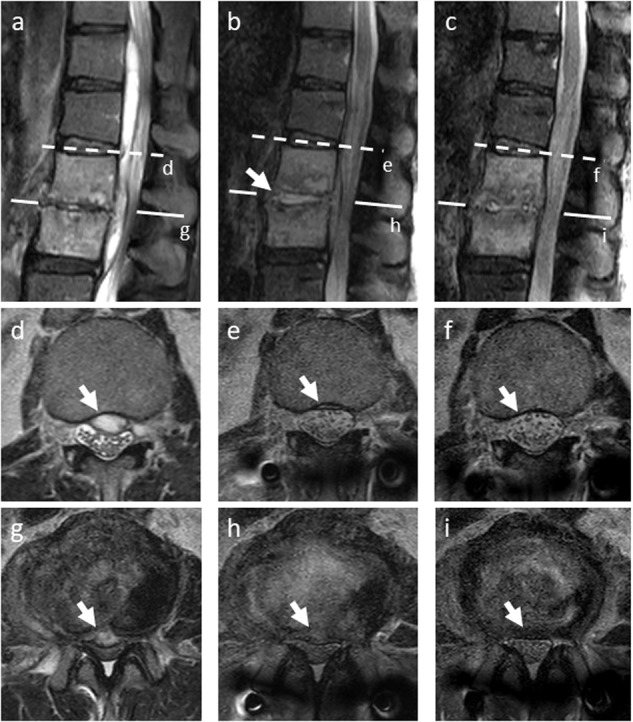

Fig. 3. Pre- and postoperative magnetic resonance imaging (MRI) of lumbar spine.

Sagittal images of MRI (short tau inversion recovery sagittal image) taken pre-operatively (a), a week after surgery (b), and two months after surgery (c); Post-operatively, epidural abscess had decreased and L2–L3 disc space had widened and collected a considerable amount of intradiscal fluid (b, arrow); Axial images of MRI (T2-weighted images) taken preoperatively (d, g), a week after surgery (e, h), and two months after surgery (f, i); The epidural abscess rapidly decreased a week after surgery (e, h, arrows), and disappeared two months after surgery (f, i, arrows).